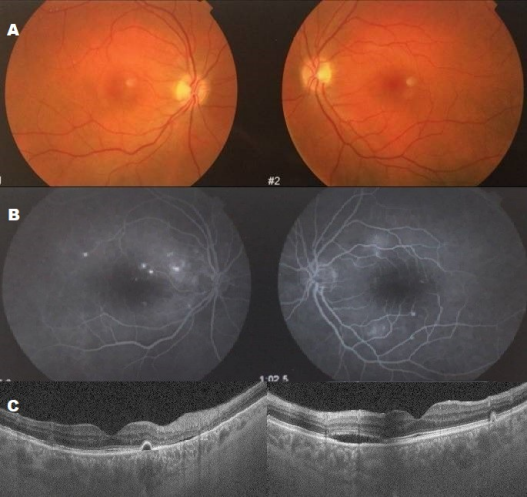

A 38-year-old woman with metastatic melanoma was treated with ipilimumab (3 mg/kg every 3 weeks). After her third dose, she began experiencing painless bilateral vision loss. Visual acuity was 0.16 in the right eye (OD) and 0.20 in the left eye (OS). Fundus examination revealed multifocal bilateral serous retinal detachments (SRDs) (Figure 1A [Fig. 1]). Fluorescein angiography (FA) showed multiple areas of leakage (Figure 1B [Fig. 1]), and OCT confirmed serous detachments of the retinal pigment epithelium (RPE) (Figure 1C [Fig. 1]). There was no evidence of active intraocular inflammation in either eye.

Figure 1: A: Fundus photographs showing multiple serous retinal detachments with retinal pigment epithelium (RPE) detachment in both eyes. B: Fluorescein angiography showing multifocal bilateral hyperfluorescent spots at the posterior pole with subretinal leakage and dye accumulation. C: OCT revealing hyporeflective areas beneath the retina, suggestive of subretinal fluid, associated with bilateral RPE detachment